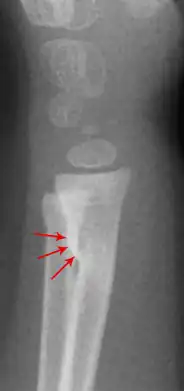

Ein Wulstbruch (auch Torusfraktur) ist – ähnlich der Grünholzfraktur – ein unvollständiger Knochenbruch, bei dem die Knochenhaut (das Periost) meist unverletzt bleibt.

Diese Art der Fraktur kommt vor allem bei den langen Röhrenknochen (Speiche (Radius), Schienbein (Tibia), Oberschenkel (Femur)) oder beim Schlüsselbein (Clavicula) vor, solange diese Knochen noch im Wachstum sind. Durch eine Stauchung wird der Knochen an der Bruchstelle wie zu einem Wulst verdickt, daher der Name.